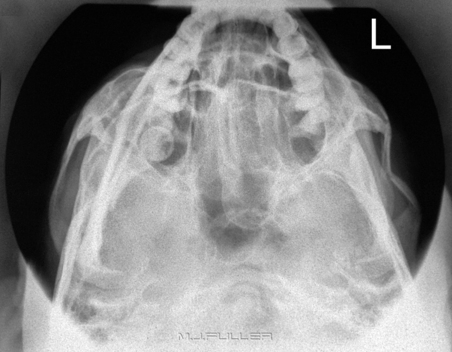

(1) 전후방향 촬영(AP projection)

X선속이 인체의 앞면에 입사되어 뒷면으로 나아가는 촬영방향입니다.

Chest검사 시 X선속을 받아들이는 상수용체(IR)에는 등이 닿게 되겠네요.